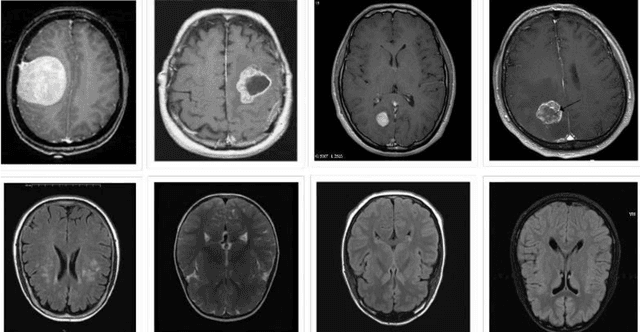

Abstract:The growth of abnormal cells in the brain's tissue causes brain tumors. Brain tumors are considered one of the most dangerous disorders in children and adults. It develops quickly, and the patient's survival prospects are slim if not appropriately treated. Proper treatment planning and precise diagnoses are essential to improving a patient's life expectancy. Brain tumors are mainly diagnosed using magnetic resonance imaging (MRI). As part of a convolution neural network (CNN)-based illustration, an architecture containing five convolution layers, five max-pooling layers, a Flatten layer, and two dense layers has been proposed for detecting brain tumors from MRI images. The proposed model includes an automatic feature extractor, modified hidden layer architecture, and activation function. Several test cases were performed, and the proposed model achieved 98.6% accuracy and 97.8% precision score with a low cross-entropy rate. Compared with other approaches such as adjacent feature propagation network (AFPNet), mask region-based CNN (mask RCNN), YOLOv5, and Fourier CNN (FCNN), the proposed model has performed better in detecting brain tumors.